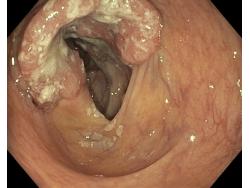

Nowotwory przewodu pokarmowego